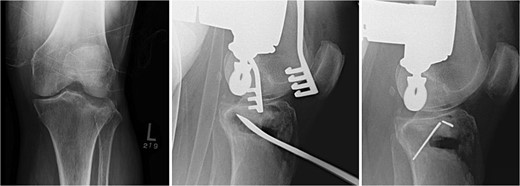

A 3.5 locking compression plate (LCP) proximal tibia plate is selected and centered on the bone to buttress the lateral condyle and the allograft. The plate is temporarily fixed with two K-wires proximally and distally. When satisfied with the plate position, a 2.5 mm drill bit and a universal drill guide are used to drill bicortically into the axilla, just distal to the apex of the fracture. After measurement of the required length with a depth gauge, a 3.5 mm screw is placed. The same process is repeated in a percutaneous fashion to place a distal 3.5 mm screw through a stab incision. Proximal 3.5 mm locking or non-locking screws, based on surgeon preference and bone quality, are filled using the 2.8 or 2.5 mm drill bit, respectively. The K-wires are removed, and final x-rays are obtained. The medial proximal tibial angle and posterior slope are measured and compared to the contralateral extremity (Fig. 3).

Fracture fixation using 3.5 mm LCP proximal tibia plate, rafting screws, and tricortical iliac crest allograft holding the articular surface.